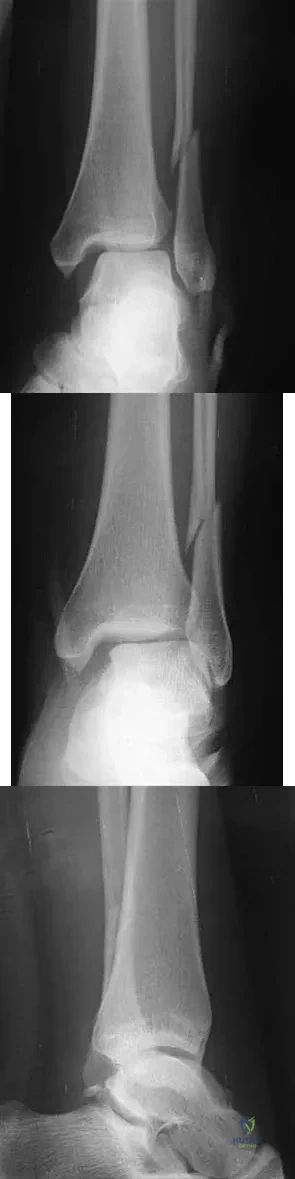

A 25-year-old woman has significant pain and swelling in her left ankle after falling off her bicycle. Examination reveals that she is neurovascularly intact. Radiographs are shown in Figures 33a through 33c. What is the next most appropriate step in management?